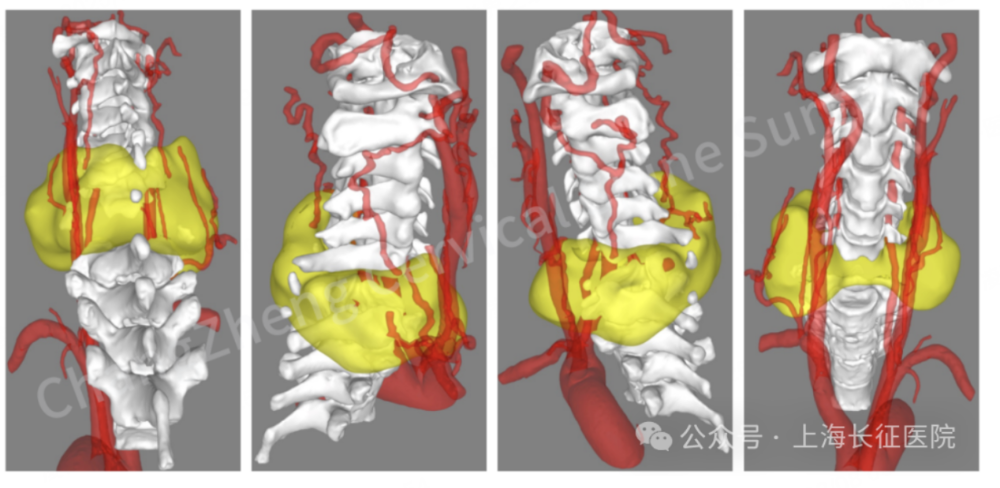

眼前这位患者,几乎已被宣判“死刑”。影像学检查显示,患者发生了罕见的大跨度颈椎离断式脱位,脊髓严重挫伤、关键的神经血管结构撕裂。

影像检查显示患者颈椎罕见大跨度脱落

CT三维重建提示颈椎离断部位情况严重复杂